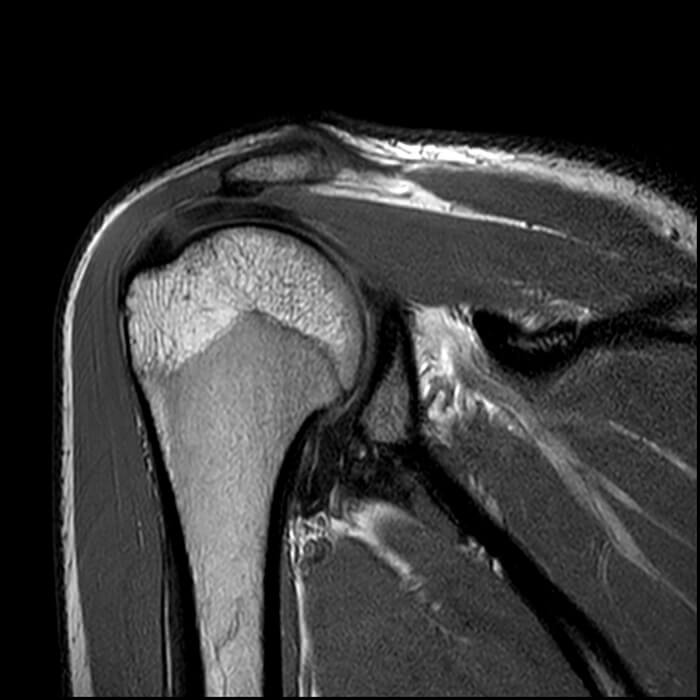

För att visa att jag inte bara pratar – här är mina MR-resultat före och efter.

Artros, artrit eller osteoporos är inte alltid lätta att känna igen – och med åldern drabbas nästan alla. Efter 50 års ålder har 93 % av människor tecken på degenerativa förändringar i broskvävnaden. Det är nästan omöjligt att helt skydda sig från ledproblem. I den här artikeln beskrivs ett fall av artros i axelleden – en särskilt komplicerad form, eftersom leden ligger djupt under musklerna och är svår att påverka direkt.